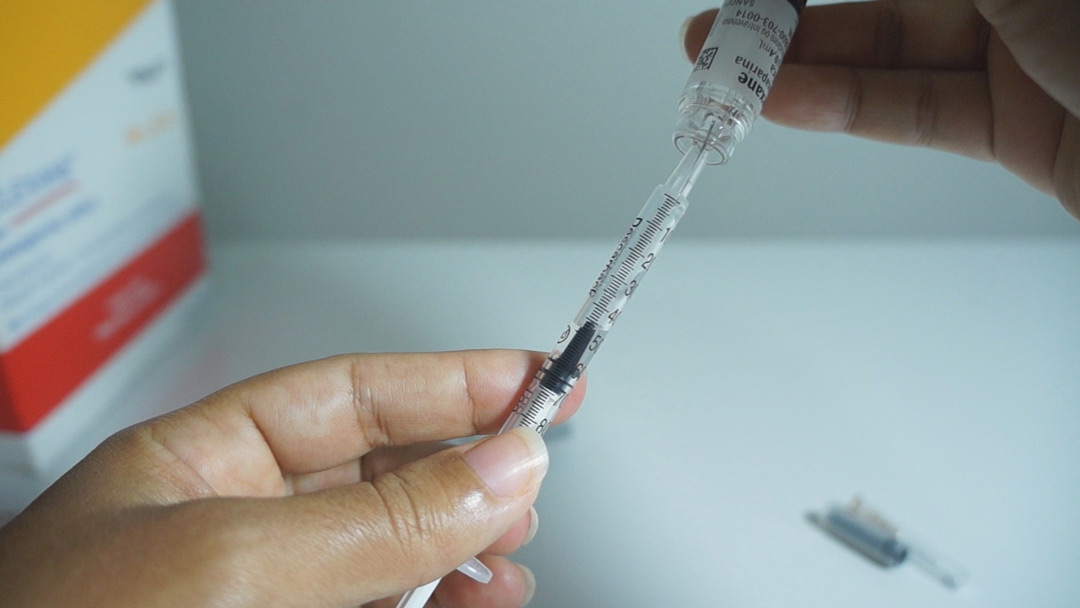

Como fracionar?

Você vai precisar de uma SERINGA DE INSULINA, de 1ml.

Precisa ser da seringa que solta a agulha.

Uso duas seringas de enoxaparina de 40mg, uma uso completa e outra só uso 20mg, o restante que sobra uso no outro dia.

Então, coloco na seringa de insulina 20mg – 0,2 ml, depois completo com os 40mg – 0,4ml totalizando 60mg – 0,6 ml que preciso.

Puxo um pouco até a marca do 70, pra formar uma bolinha de ar, faço com que essa bolha vá para o fundo da seringa e aplico. (Assista o vídeo).